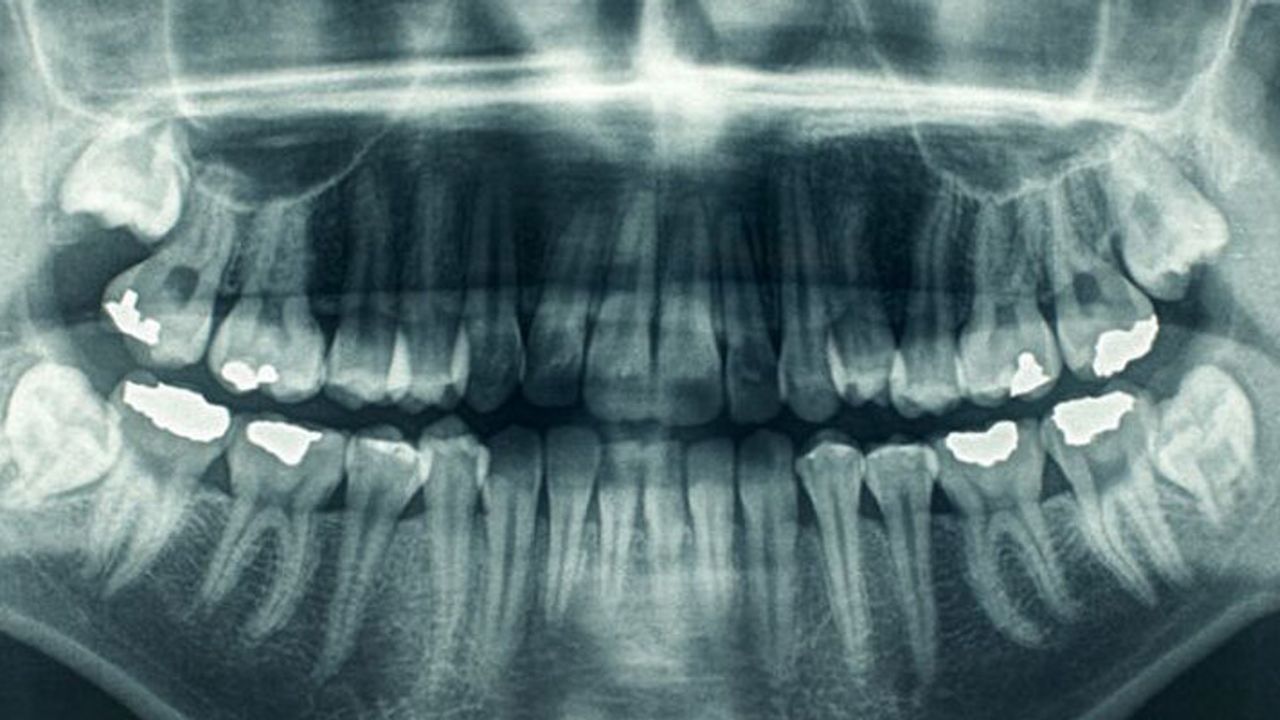

Nottingham ve Harvard Üniversitesi’nden bir grup bilim insanı, diş çürüklerini tedavi etmenin yeni bir yolunu bulduğunu öne sürüyor. Araştırmacıların geliştirdiği yeni kök hücre diş dolgusu, dişlerin kendini tedavi etmesine olanak tanıyor.

Kullanılan dolgu, kök hücrelerin diş kemiği büyümesini teşvik etmesi ile etki ediyor. Diş kemiğini, dişin büyük bölümünü oluşturan kemiksi kısım olarak tanımlamak mümkün.